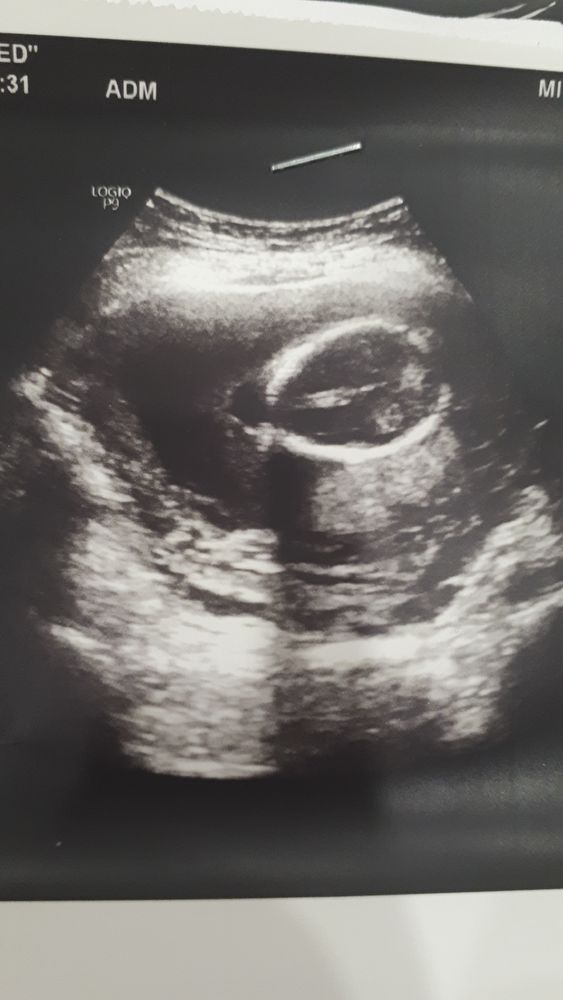

Этл с Интернета. Вот у мальчика тоже белое пятно (писюн я так понимаю) над мошонкой.

Я честно сама ни бум-бум, но у нас было вот так (то самое кофейное зернышко), многие здесь голосовали за девочку))) узист давал 80% на мальчика в 16 недель. Плюнули и сдали тест, результат вы видите)))